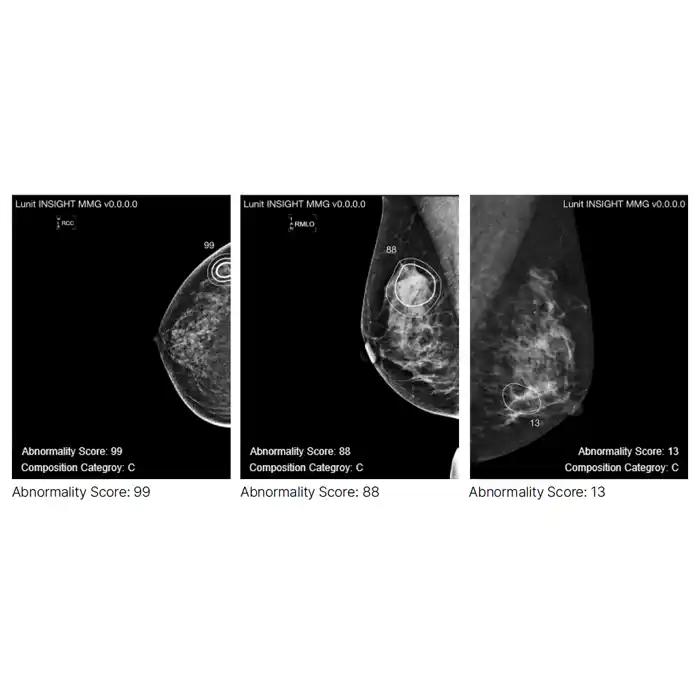

Lunit INSIGHT MMG and DBT

Lunit INSIGHT MMG and DBT are AI-powered diagnostic solutions designed to support breast cancer detection in mammography (MMG) and digital breast tomosynthesis (DBT). INSIGHT MMG analyzes 2D mammograms to identify suspicious lesions, quantify malignancy risk, and assist in early cancer detection—even in dense breast tissue—while reducing radiologist workload by triaging routine cases. INSIGHT DBT extends these capabilities to 3D tomosynthesis images, detecting soft tissue lesions and calcifications with high precision, providing quantitative malignancy scores, and streamlining image review. Both solutions are FDA-cleared and CE-certified, integrating seamlessly into clinical workflows to enhance accuracy, efficiency, and confidence in breast imaging.